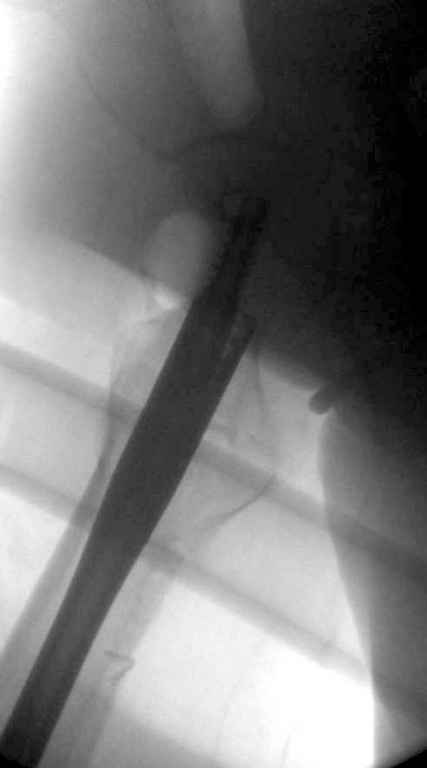

В приложении похожий пример, к счастью, пациентка появилась не после, а "за полчаса" до протрузии. Пересинтезировали с исправлением ошибок.